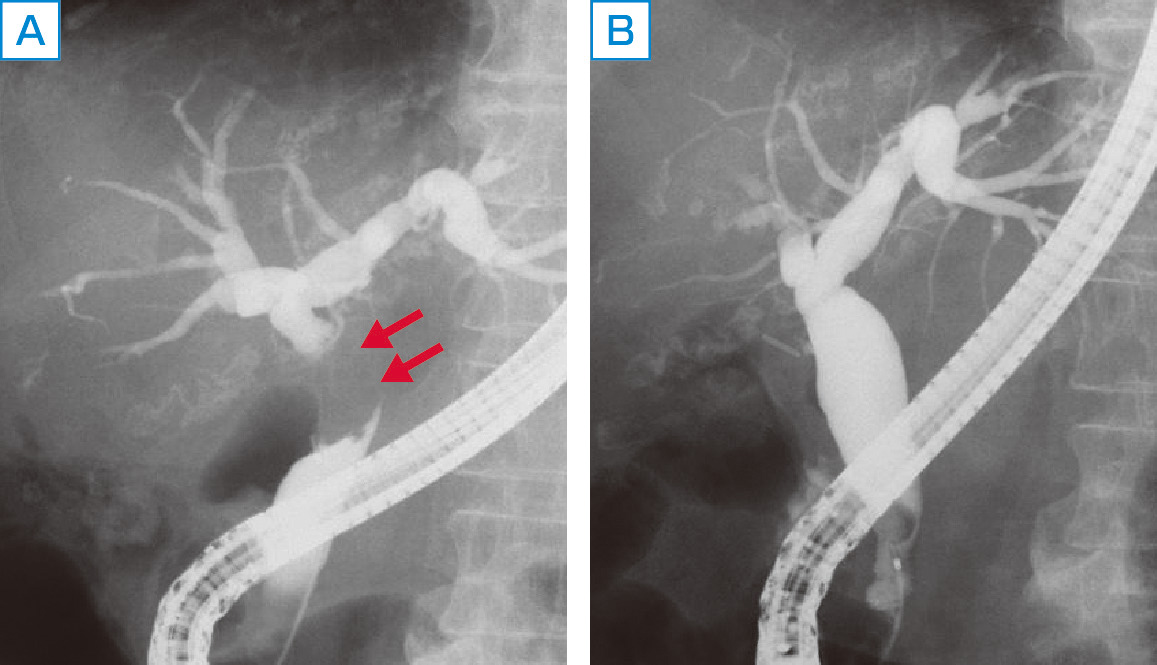

ⓔ図12-25-6 Mirizzi症候群 A:胆嚢頸部の陥頓結石により総胆管圧排. B:胆嚢摘出後,総胆管狭窄は改善.